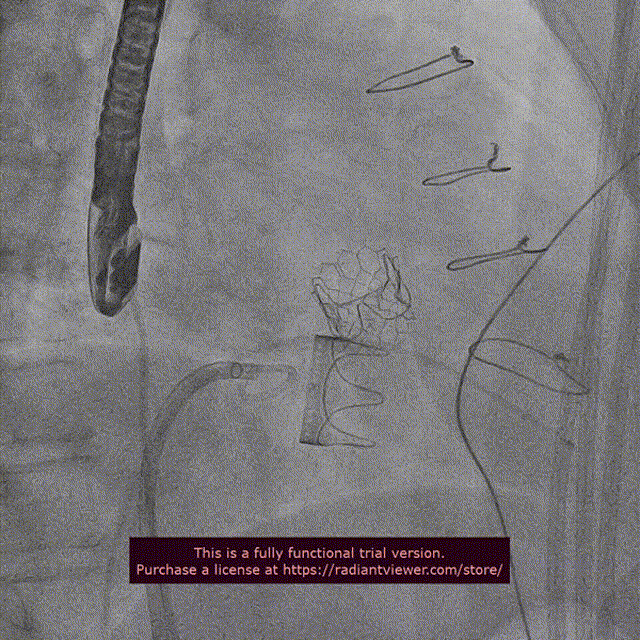

近日,中国医学科学院阜外医院潘湘斌教授团队,在多科室的通力配合下,凭借扎实的手术功底顺利完成一例经导管主动脉瓣和二尖瓣瓣中瓣置换术。

手术过程